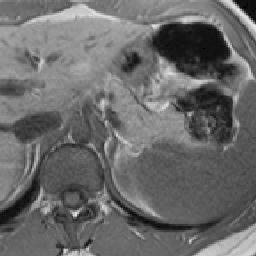

Finally, Fig. 9 displays examples of output probability maps from all of the comparative methods, i.e., HNN [12], UNet [16], PNet-MSA and “PNet-MSA+BiRNN”, where the latter one delivers the sharpest and clearest output on both CT and MRI datasets. More specifically, PNet-MSA presents results that are detailed and recover the major part of the pancreas, where both HNN and UNet suffer from significant low segmentation recall. When observing the BiRNN outputs for CT and MRI, we find detailed pancreas parts in CT have been recovered via shape continuity learning and regularization, while in MRI, the BiRNN only outputs probability map with the same shape in PNet-MSA’s output, which is optimal when the inter-slice shape changes drastically in the MRI dataset. Thus, BiRNN would help to refine pancreas segmentation with a smoothed surface in the situation that slice thickness of the 3D scans is reasonably small, e.g., <2absent2<2mm.

Figure 9: Examples of output probability map: columns from left to right are the input CT/MRI image, results from HNN [12], UNET [16], the proposed PNet-MSA sub-network, and the full CNN-RNN (“PNet-MSA+BiRNN”), and the ground truth. Our model delivers the most clear probability maps which preserve detailed pancreatic boundaries.